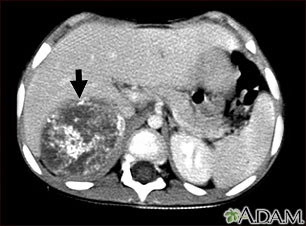

Neuroblastoma is a very rare type of cancerous tumor that develops from nerve tissue. It usually occurs in infants and children.

Neuroblastoma can occur in many areas of the body. It develops from the tissues that form the sympathetic nervous system. This is the part of the nervous system that regulates body functions, such as heart rate and blood pressure, digestion, and levels of certain hormones.

Most neuroblastomas begin in the abdomen, in the adrenal gland, next to the spinal cord, or in the chest. Neuroblastomas can spread to the bones. Commonly affected bones include those in the face, skull, pelvis, shoulders, arms, and legs. It can also spread to the bone marrow, liver, lymph nodes, skin, and around the eyes (orbits).

- CT scan of chest and abdomen

- MRI scan of chest and abdomen